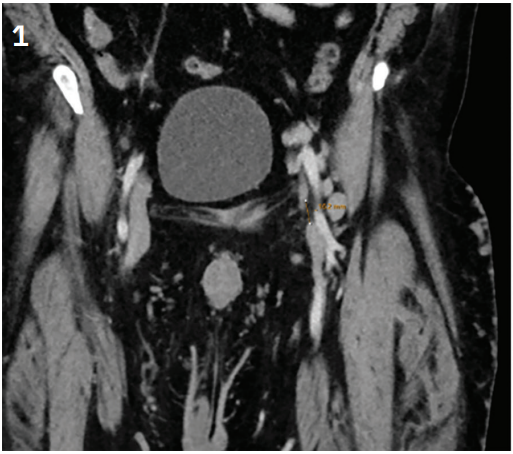

CLD Tiede Figure 1, reprint from VDMChronic venous disease is associated with significant patient morbidity, and not all cases are easily managed with traditional techniques. We report a case of common femoral vein occlusion in a patient with Klippel-Trénaunay syndrome. Successful reconstruction of the patient’s common femoral vein was made possible using the gun-sight technique, originally developed by Haskel et al for intrahepatic interventions. This case highlights the adaptability of endovascular methods and underscores the role of interventional radiology in providing novel therapeutic options for patients previously without hope.

Dr. Tiede describes using a modified gun-sight recanalization approach to reconstruct an absent/occluded common femoral vein in a patient with severe chronic venous disease. A step-by-step discussion of the gun-sight technique is available in the Appendix.